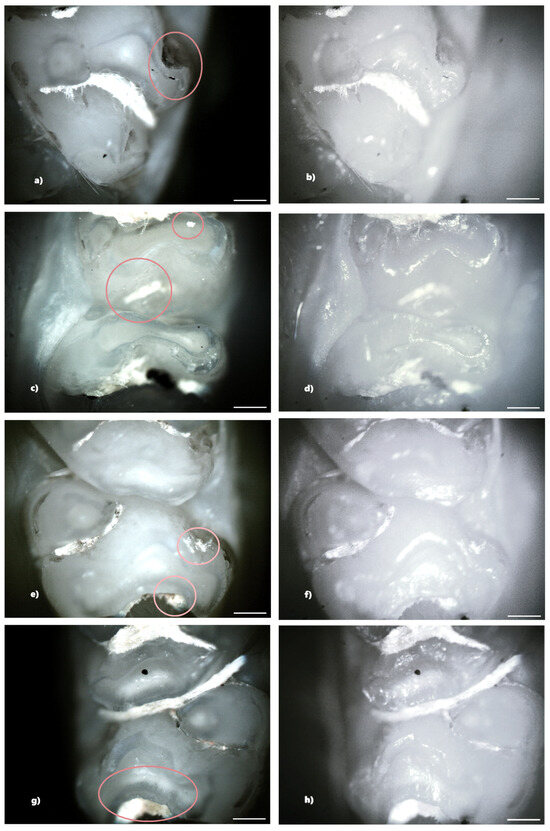

In the standard dose ibuprofen group (8 mg/kg), 11 rats (73.33%) showed at least one clinical form of DDE. Of these, two rats showed hypoplasia and five rats showed demineralization. In addition, three rats showed both clinical forms of DDE. Within this group, from a total number of 240 teeth, 33 teeth (13.75%) presented at least one clinical form of DDE, respectively, 15 incisors (45.45%) and 18 molars (54.55%), and according to the clinical form of DDE, 7 teeth (21.21%) showed hypoplasia (molars) and 26 teeth (78.79%) showed demineralization (15 incisors and 11 molars). Each tooth with DDE had only one affected surface, resulting in a total of 33 affected tooth surfaces (Figure 7).

Figure 7. Demineralization on the occlusal surface of some molars (a,c,e—PLM image, cross polarizers, 4× objective; b,d,f—BFM image, 4× objective) and on the mesial surface of a molar (g—PLM image, cross polarizers, 4× objective; h—BFM image, 4× objective). Scale bar represents 500 μm.